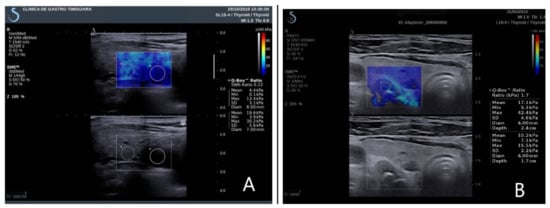

The examiner maintained precise adherence for a minimal 6 s to the probe on the examination area, not applying any manual compression, permitting the transducer to induce acoustic vibrations in the parathyroid tissue; after image stabilization, a real-time elastogram overlapped on the B-mode image, determining a color map (Figure 1). After image stabilization, on a frozen image, quantitative measurements were performed on parathyroid tissue, thyroid, and muscle tissue. All patients were examined by two clinicians, one with over 15 years of experience in elastography and neck ultrasound. Five measurements were performed and recorded for each parathyroid gland evaluated. We determined and analyzed the median results of all the quantitative measurements.

Figure 1. Elastograms overlapping on the B-mode image. (A) Right inferior parathyroid adenoma in primary hyperparathyroidism; (B) right inferior parathyroid hyperplasia in secondary hyperparathyroidism.